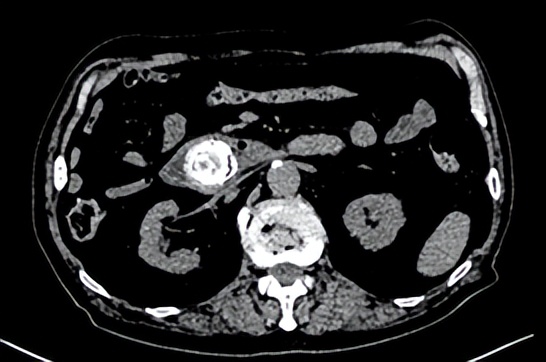

于爷爷三天前进食了一些柿子后出现上腹部不适,伴有恶心呕吐症状,逐渐连水也喝不下,人迅速萎靡、衰弱,后来出现腹胀腹痛,到急诊就诊,腹部CT检查发现十二指肠水平段高密度影,继发胃部扩张(图1),遂收入消化内科继续治疗。

图1